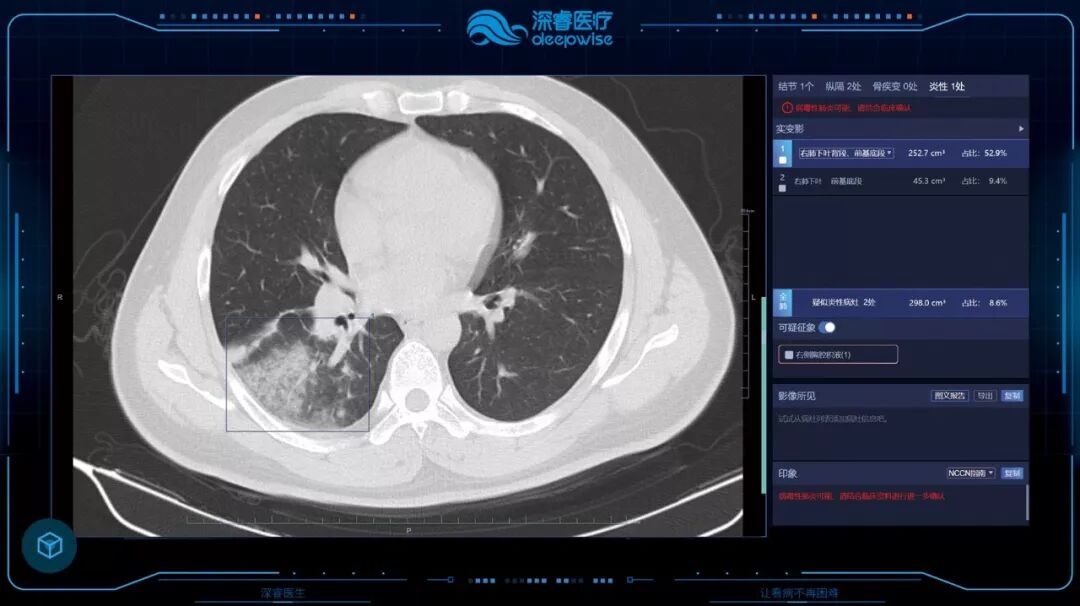

新型冠状病毒发展迅速、在目前医疗资源紧张,医务工作人员工作量剧增的严峻形势下,借助人工智能技术可以高效的辅助当前新冠肺炎病例的大规模影像筛查,有助于及时发现潜在的患者,加强防控。Dr.Wise®肺部疾病智能解决方案(新冠肺炎增强版)提供全流程的诊疗管理,包括定位、定量分析、肺部CT炎症的多时点随访,标准结构化报告等,辅助医生大幅提升诊断效率,同时提高诊断准确性。无论是影像疑似病例确认为影像诊断病例,还是转归期患者确诊,多次CT复查随访都是必不可少的。“肺部疾病智能随访系统”可以针对同一患者的随访检查进行智能分析,对比病灶的变化情况,辅助医生对病情进展进行准确判断。